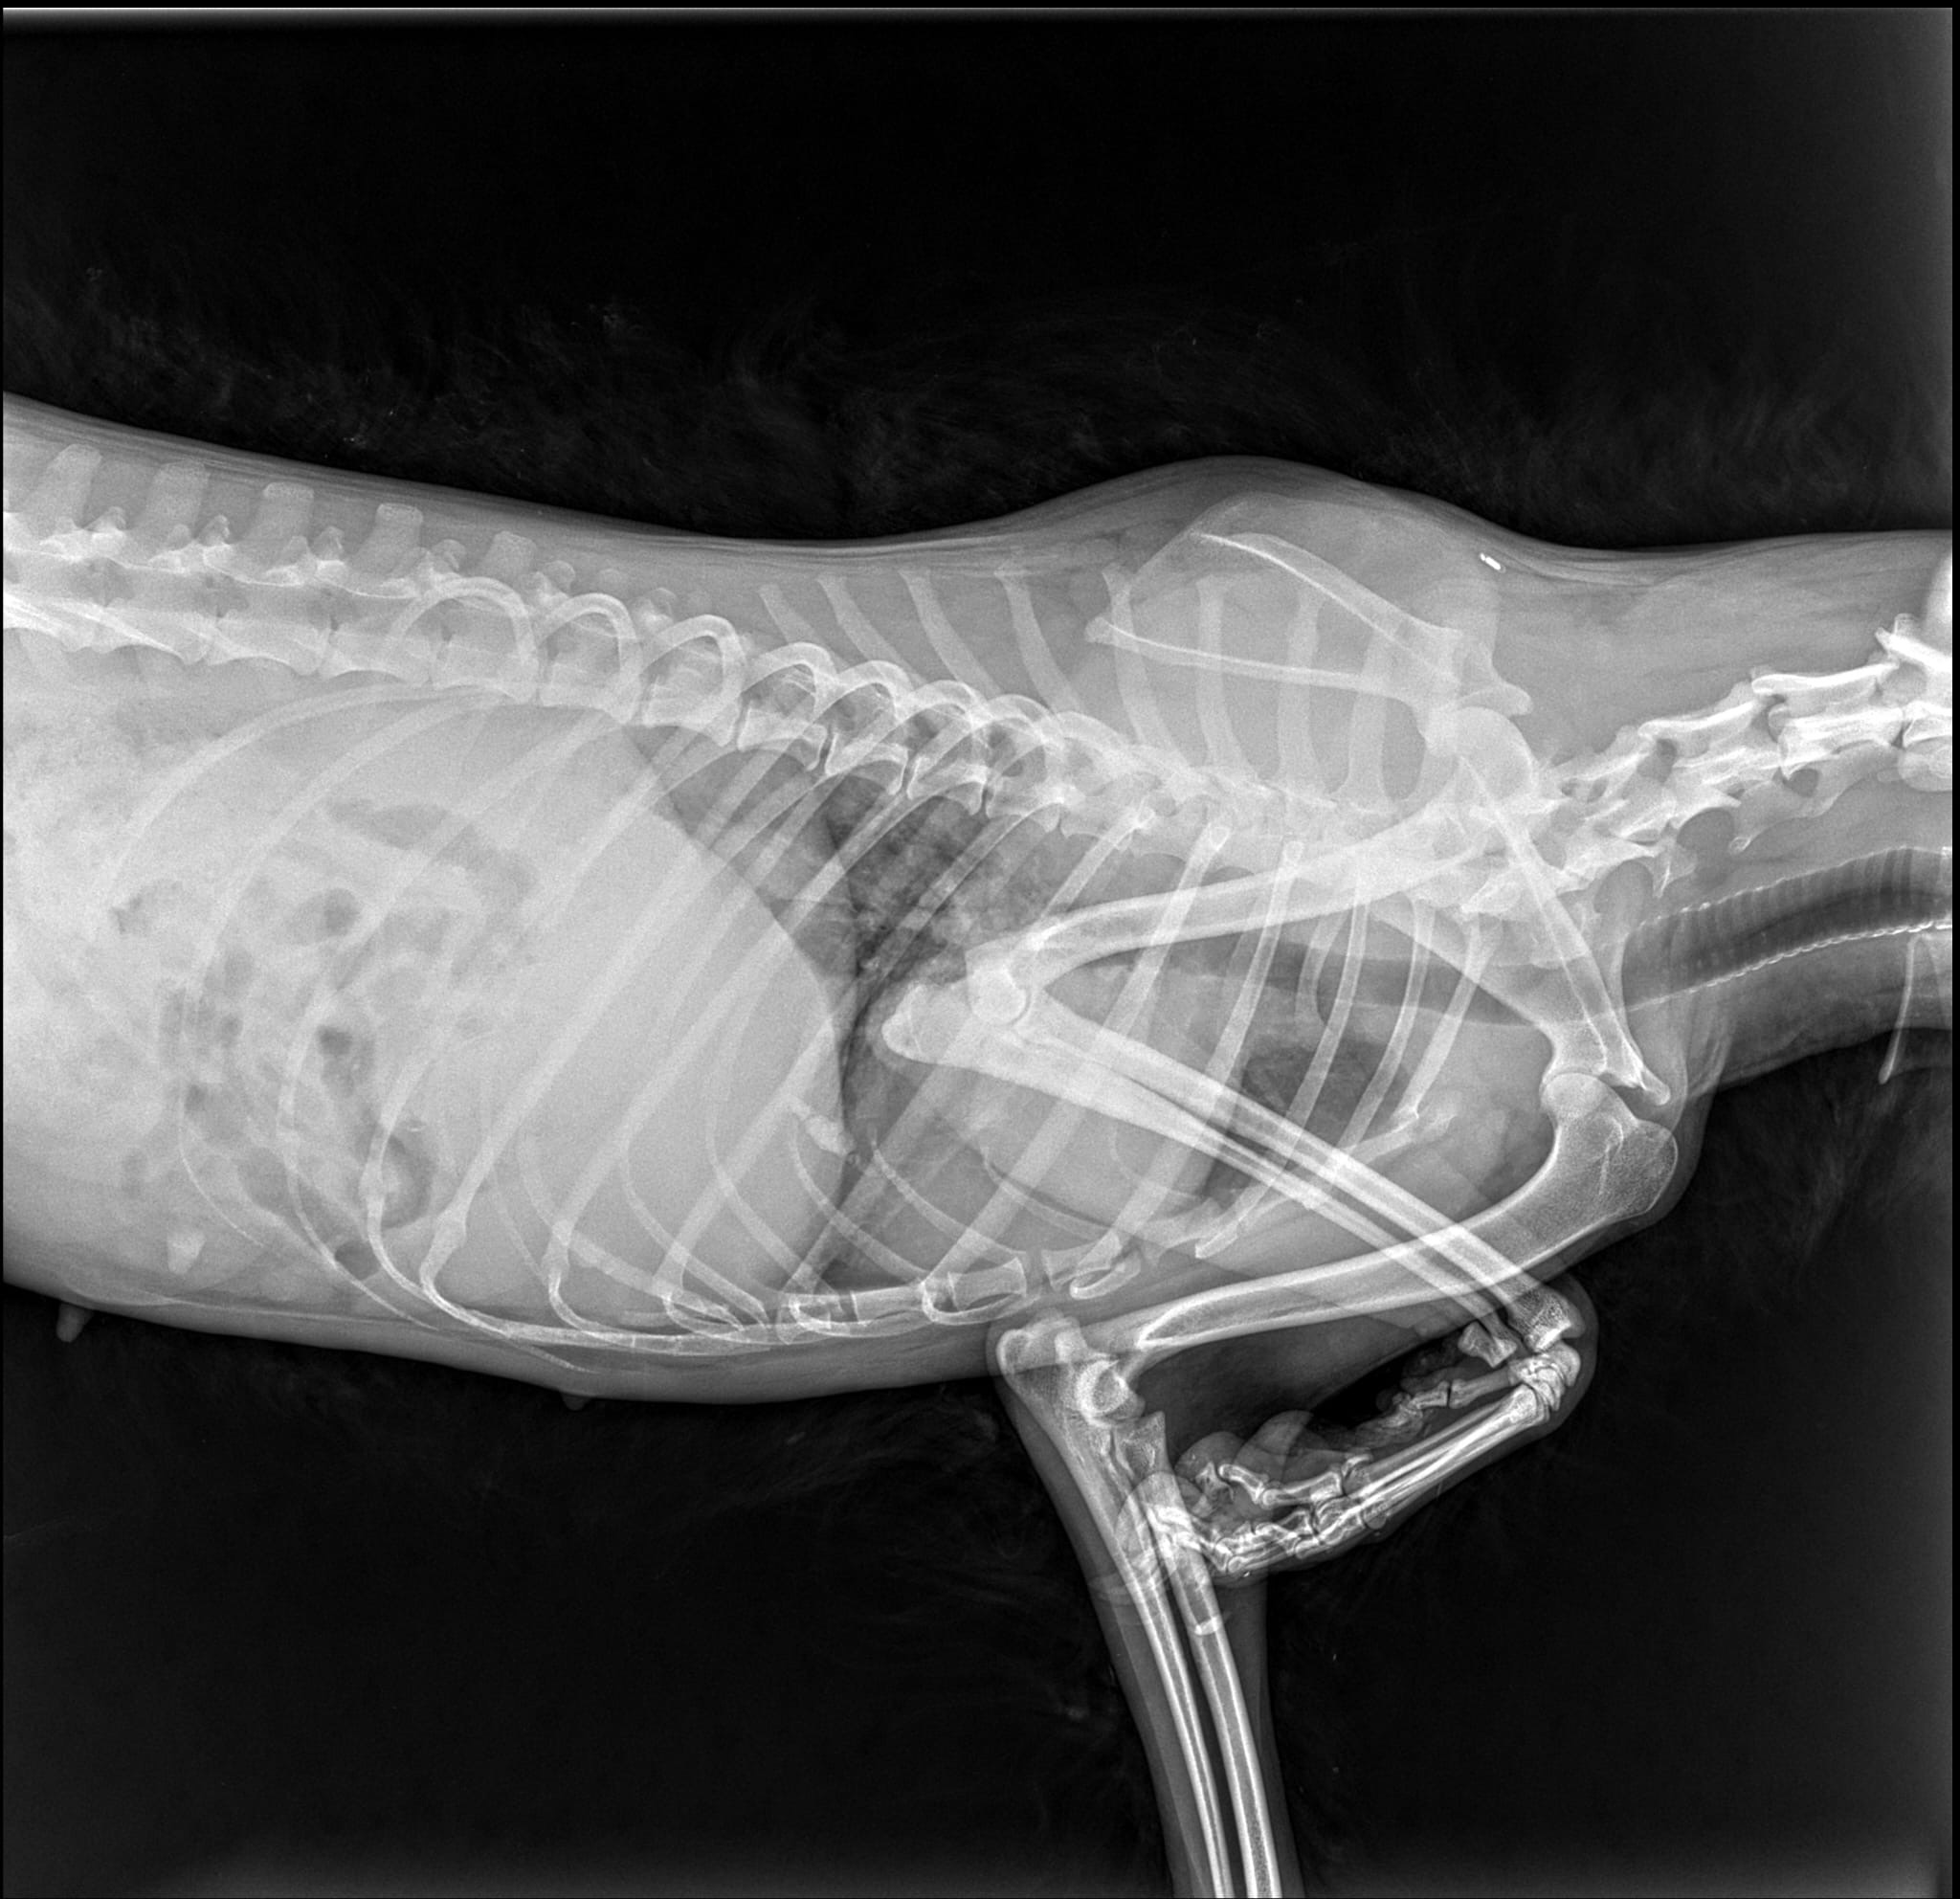

Wir haben Flöckchen nach Bukarest in eine Klinik gesandt, um zu schauen, ob man sie operieren kann. Sie wurde geröngt und man teilte uns mit, das man Flöckchen leider nicht operieren kann. Ihr Ellbogen ist verletzt. Sie hat laut Tierarzt eine Ellbogendysplasie und durch die Verletzung auch schon Arthrose.